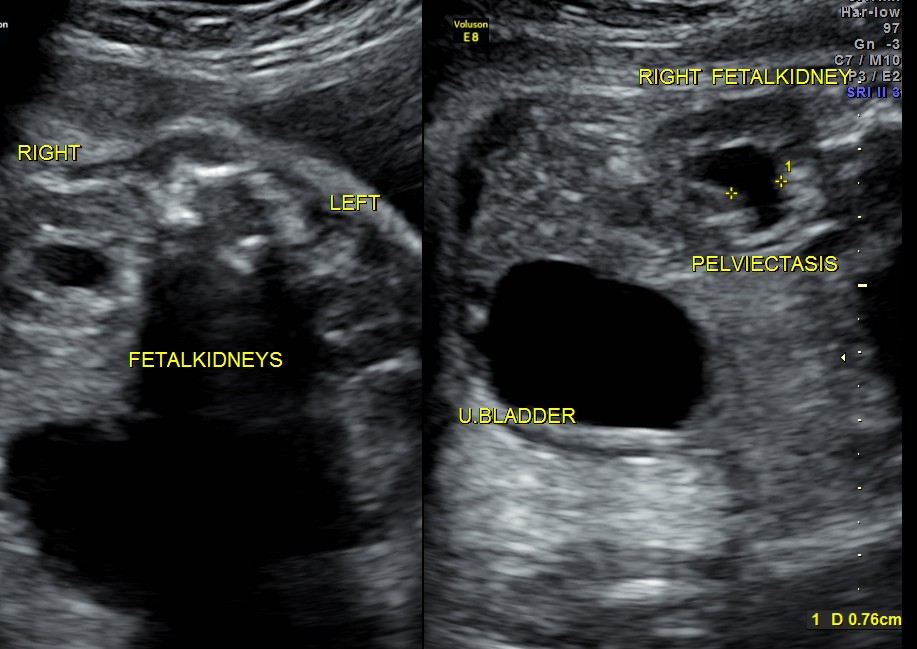

This was a 26-year-old lady with no history of consanguinity. The scan was done at 35 weeks of gestation.

Right fetal kidney shows mild pelviectasis.